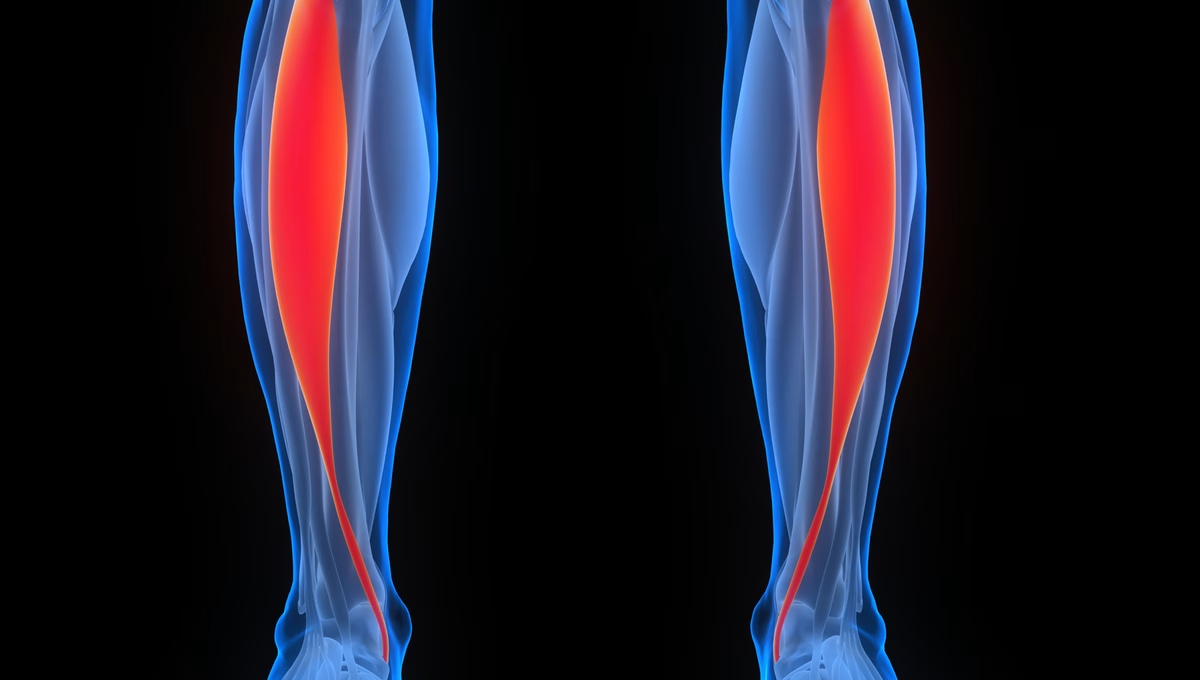

Der Tibialis anterior (Musculus tibialis anterior) ist ein langer, oberflächlich gelegener Muskel der unteren Extremität. Er gehört zu den Extensoren des Unterschenkels und ist damit der vorderen Gruppe der Unterschenkelmuskulatur zugehörig.

Der Ursprung des Muskels sind der Condylus lateralis und die proximalen zwei Drittel der lateralen Fläche (Facies lateralis) der Tibia. Zusätzlich entspringen seine Fasern von der Membrana interossea cruris und von der Fascia curis superficialis. Er setzt plantar am Os cuneiforme mediale und Os metatarsi I an, indem die Sehne unter dem Retinaculum extensorum superius und inferius medial vom Sprunggelenk zum Fuß verläuft. An der Ansatzstelle befindet sich naheliegend die Bursa subtendina musculi tibialis anterioris, also ein Schleimbeutel.

Der Musculus tibialis anterior liegt an der Vorderseite des Unterschenkels oberflächlich. Er befindet sich in der Extensorenloge, im anterioren Kompartiment entlang der Tibua bis zur Plantarseite des Fußes.